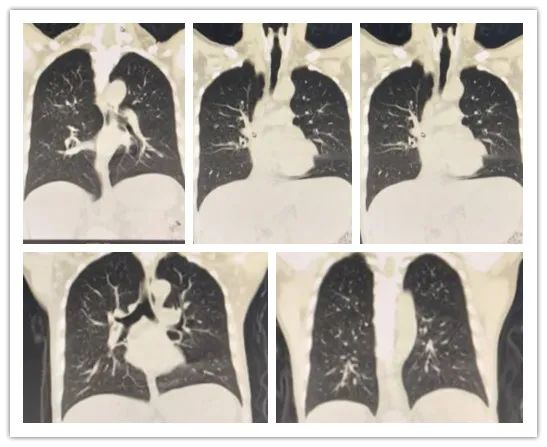

李某,男,26岁,白血病病史,行胸部CT检查,排除肺部浸润情况。

影像所见:

双肺纹理增粗、模糊,双肺见弥漫性斑点状阴影;中肺野见小团片状影,边界尚清,大小约2.1×3.3cm,周围见小斑片模糊影及条索影,邻近胸膜受牵拉,粘膜增厚。

冠状位图像

冠状位见双肺纹理增粗、模糊,双肺见弥漫性斑点状阴影。

矢状位图像

矢状位见双肺纹理增粗、模糊,双肺见弥漫性斑点状阴影。